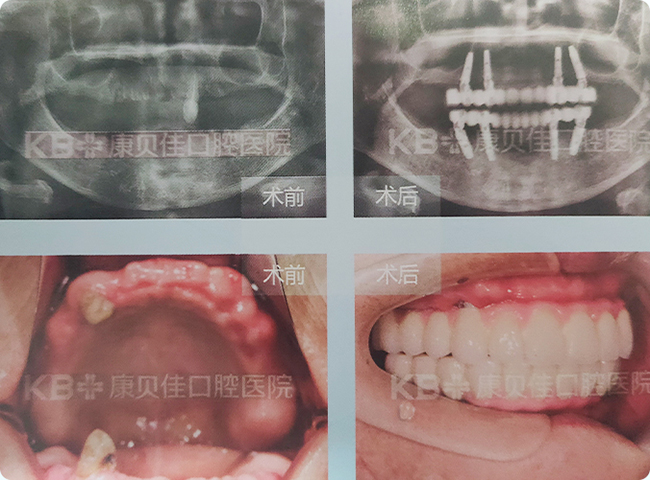

王女士 80岁

牙齿40多岁开始出现问题,戴过活动假牙,感觉异物感强,硬的粘的吃不了,参加了康贝佳几次活动后想种牙,到康贝佳采用上下各种植4颗体恢复了满口牙。

治疗方案:

上颌种植4颗修复半口 下颌种植4颗修复半口